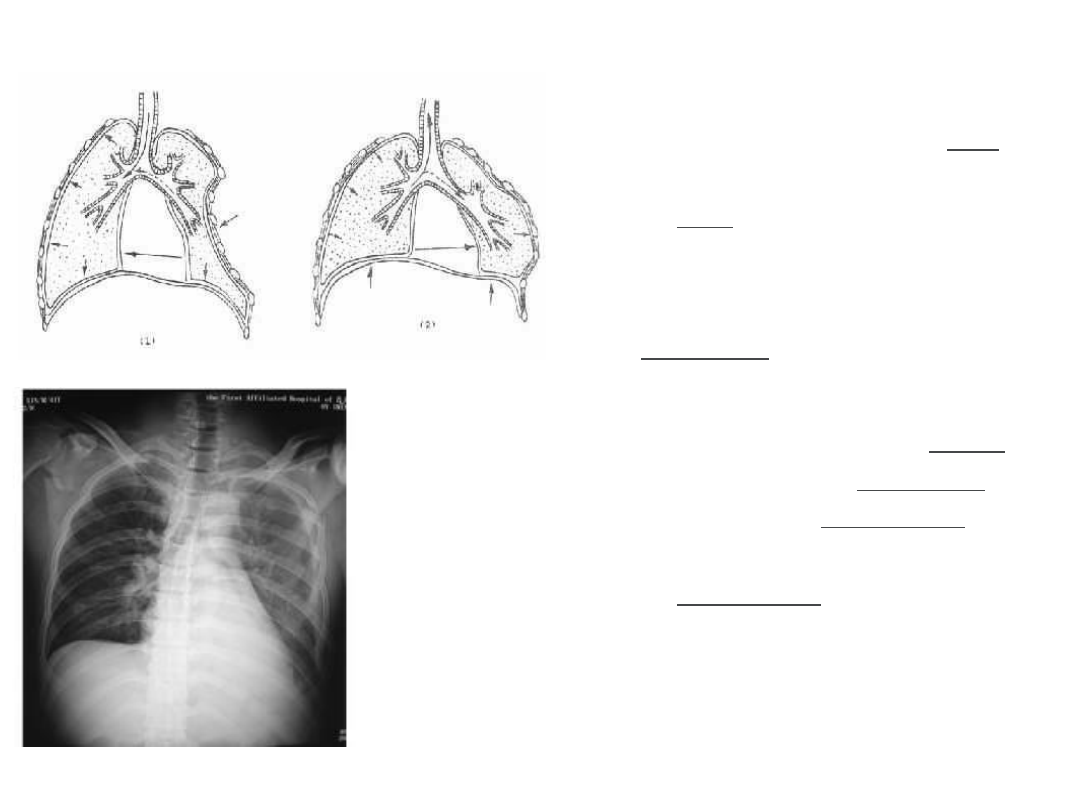

连枷胸:肋骨骨折最严重

的形式。损伤肋骨

≥3

根并

且每根肋骨有

2

处以上的骨

折。易形成浮动胸壁。在

胸腔负压存在的情况下出

现反常呼吸。对肺的气体

交换及循环的影响极大。

必须立即处理。

连枷胸